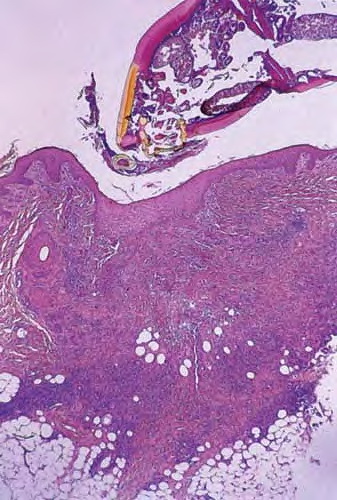

Tick bite =عضة القراد